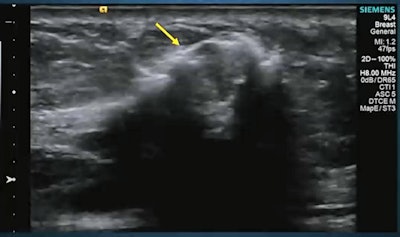

Sentinel lymph nodes can be identified through contrast-enhanced ultrasound lymphosonography (pictured), rivaling that of blue dye and radioactive tracers, according to research presented at the RSNA annual meeting. Image courtesy of Dr. Priscilla Machado.Comparison with the blue dye reference standard showed that lymphosonography had 73% accuracy while the radioactive tracer's accuracy was 72%, although this did not achieve statistical significance.